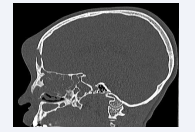

A contrast-enhanced CT scan was performed, and revealed the presence of an enhanced collection in the anterior frontal soft tissues, with a large defect in both anterior and posterior walls of the frontal sinus; complicating an active sinusitis but no abnormalities in the brain parenchyma [Figure 3,4].

Pan-sinusitis with frontal abscess.

Figure 3: Pan-sinusitis with frontal abscess.

CT scan in sagittal section: Defect of anterior and posterior walls of the frontal sinus with abscess.

Figure 4: CT scan in sagittal section: Defect of anterior and posterior walls of the frontal sinus with abscess.

Diagnosis is confirmed by contrast-enhanced CT scan, while MRI allows for better characterization of the intracranial extension [7]. In our case, an urgent craniofacial contrastenhanced CT scan was performed, revealing the presence of a collection in the anterior medial frontal soft tissues that enhanced peripherally after contrast injection. Additionally, a defect in the anterior and posterior walls of the frontal sinus was identified, complicating an active acute pan sinusitis without clear delineation of a cerebral complication.